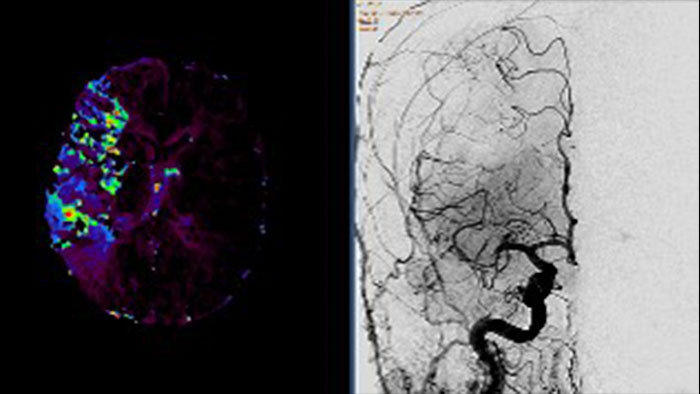

Determine areas of reduced cerebral blood flow as compared to the contralateral hemisphere

Generates qualitative and quantitative information about changes in image intensity over time. The application calculates and displays quantitative color maps of cerebral blood flow (CBF), cerebral blood volume (CBV), mean transit time (MTT) and time-to-peak (TTP), and provides summary maps which may help physicians in determining areas of reduced cerebral blood flow compared to the contra lateral hemisphere.

Contrast arterial structures with surrounding bone and soft tissue to assist in identification of vascular abnormalities

The XA Vascular Processing – DSA (in MMV) expands your workflow by allowing you to read and post-process iXR images virtually anywhere. Obtain images of arteries in various parts of the body using tools to perform standard and run subtractions, pixel shifting, and landmarking. This application also provides post-processing tools to edit and optimize the DSA XA data created in the interventional room.

Benefits

Comprehensive reviewing tool for multiple modalities, all in a single viewer

The Multi Modality Viewer (MMV) now supports viewing and post processing of angiography images and series. Review and perform analysis of angiographic imaging alongside other modalities for a comprehensive review of the patient case. Perform vascular processing of images (Digital Subtraction Angiography) – subtraction, pixel shifting and land marking. Include key images into the generic MMV report. Prior to the intervention, relevant diagnostic (MR and or CT) data can be bookmarked and automatically retrieved upon patient selection in the Allura, or the Azurion suites.